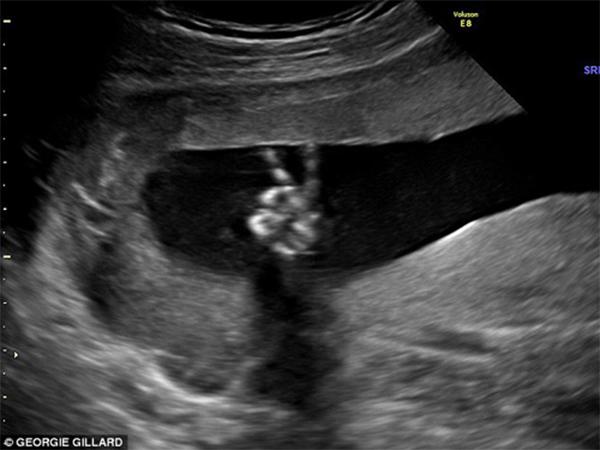

Hình ảnh thai nhi 20 tuần giơ tay biểu tượng chiến thắng.